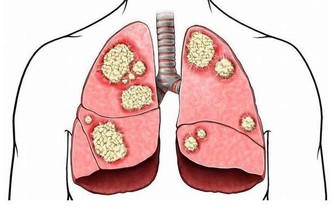

六、軀體疾病引起的繼發性抑鬱症如心髒病、肺部疾病、內分泌代謝疾病甚至重感冒、高熱等,都可引發這類抑鬱症。